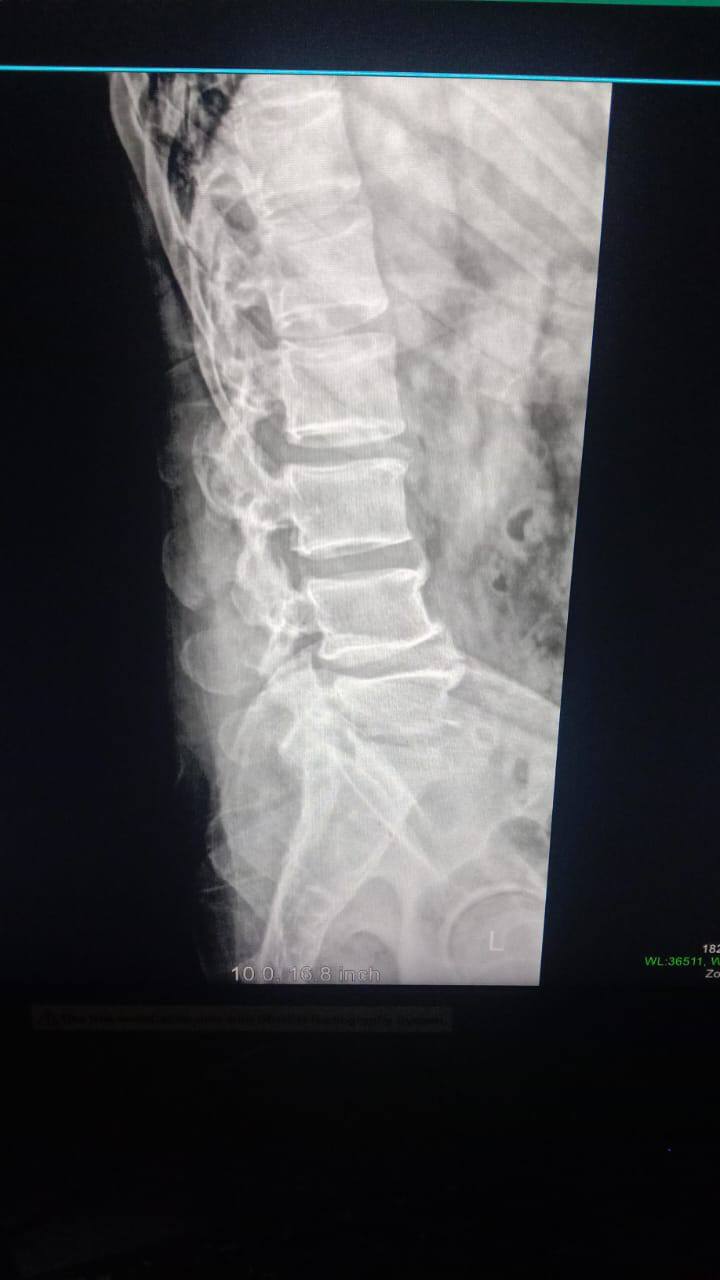

،أ.د/ جمال شمس مدير المستشفى الجامعي الرئيسي،أ.د/ حسام الدين جاد رئيس قسم جراحة العظام نجح فريق قسم جراحة العظام والكسور في إجراء عملية معقدة لالتهاب صديدي بالفقرات مسبب تآكل بالفقرات وضاغط على جذور الاعصاب الطرفية ومسبب ضعف بعضلات الطرفين السفليين مع التأثير على كافة جوانب الحياة للمريض .وقد تمكن الفريق من إزالة الالتهاب والصديد وتثبيت الفقرات وقسم جراحة العظام على أتم استعداد لاستقبال مثل هذه الحالات .